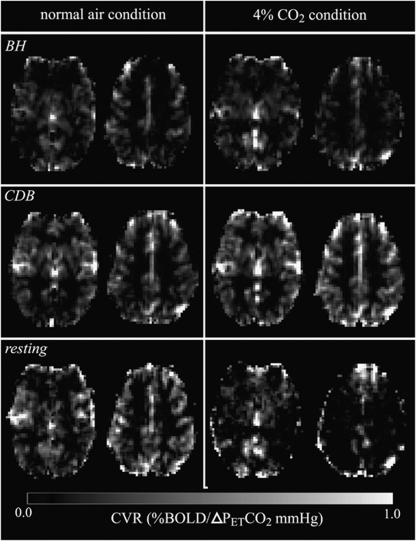

Example CVR maps derived from BH, CDB, and resting fluctuation PETCO2 regressors during each condition for a representative single subject are displayed in Figure 3 in units of %BOLD signal change per ΔPETCO2 (mm Hg). Both BH-CVR and CDB-CVR maps show good qualitative agreement, and both challenge maps reveal structural features in the brain, such as large vessels, basal ganglia, and gray and white matter contrast. The CVR maps derived from resting fluctuations appear noisier, although they occasionally reveal the same structure as respiratory challenge CVR maps.

Figure 3.

Example of slices from CVR maps for a single subject during normal air (left) and 4% CO2 (right) conditions, and derived using BH (top), CDB (middle), or resting fluctuation (bottom) PETCO2 regressors. BH, breath hold; CDB, cued deep breathing; CVR; cerebrovascular reactivity; PET, end-tidal partial pressure.